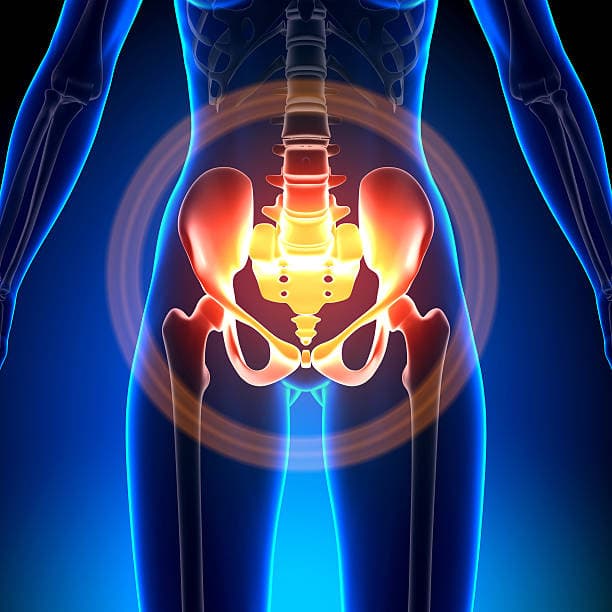

Female Pelvic – Transabdominal

Complete female pelvic ultrasound for uterus and ovaries

Uterus and Ovary Imaging

Fibroid Detection

Cyst Evaluation

Comprehensive Pelvic Assessment